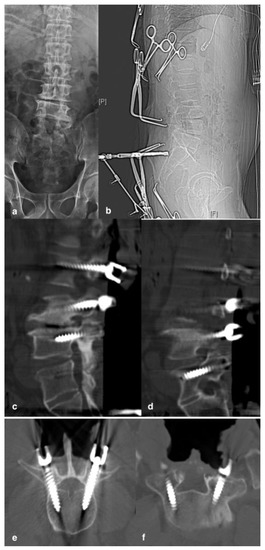

2.1. Surgical Technique

2.2. Assessment of TPS Placement

2.3. Radiographic and Clinical Analyses